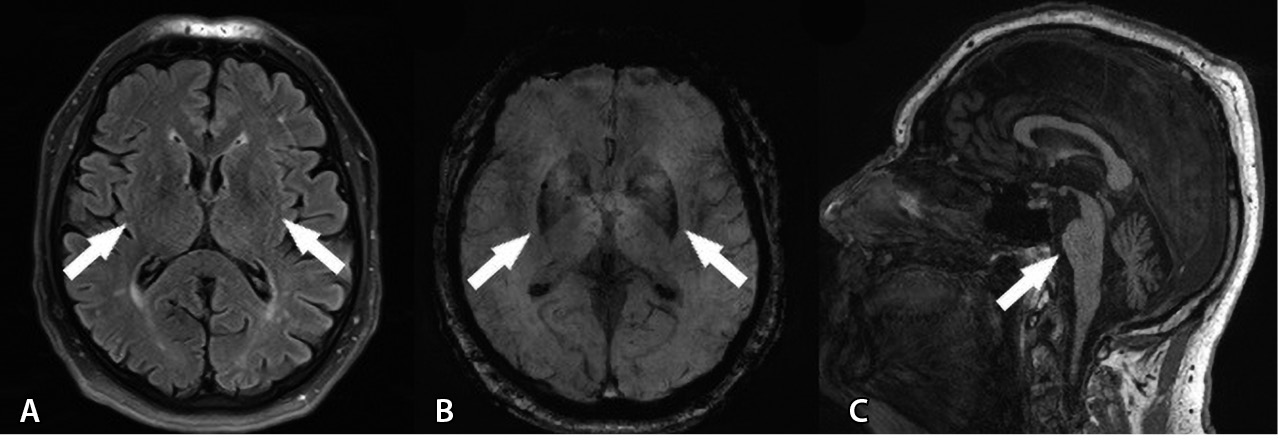

По данным УЗИ остаточной мочи ее объем составил 51 мл, по данным МРТ головного мозга в режиме T2-FLAIR выявлен линейный участок повышенного сигнала от скорлупы, гипоинтенсивный в режиме SWI, в режиме Т1 – признаки атрофии варолиева моста, мозжечка (рис. 2).

Рис. 2. Магнитно-резонансная томография головного мозга пациента А. А – Т2-FLAIR, аксиальный срез: симметричные линейные участки повышенного сигнала от скорлупы (отмечено стрелками). Б – SWI, аксиальный срез: симметрично сниженная интенсивность сигнала от скорлупы (отмечено стрелками). В – Т1-взвешенное изображение, сагиттальный срез: признаки атрофии варолиева моста, мозжечка (отмечено стрелкой)

На основании критериев диагностики МСА от 2022 г. пациенту А. был поставлен диагноз клинически достоверной МСА-П.